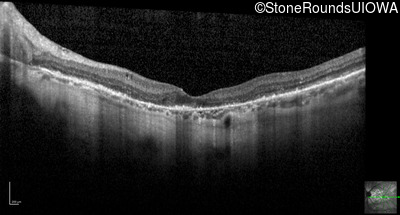

Optical Coherence Tomography - Right - 20/20 -1

Exemplar / OCT Stack